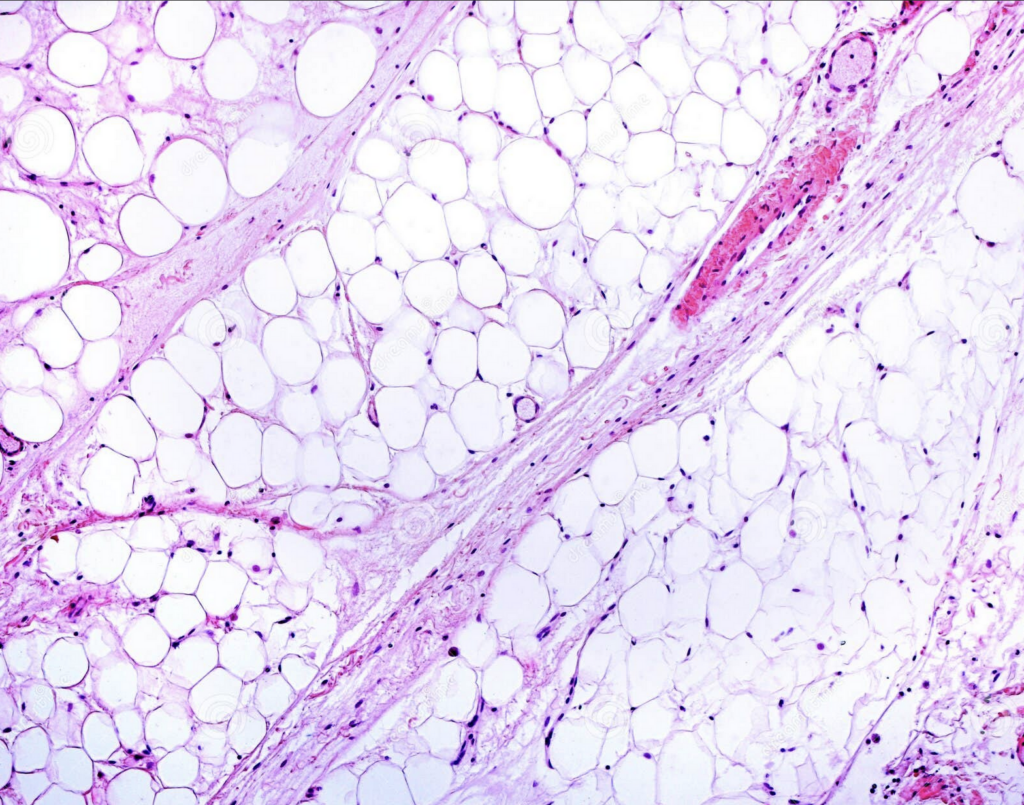

I. Définition

Le lipœdème est une maladie chronique du tissu adipeux caractérisée par une accumulation anormale et symétrique de graisse sous-cutanée, principalement au niveau :

Cette graisse est dite pathologique, car elle est :